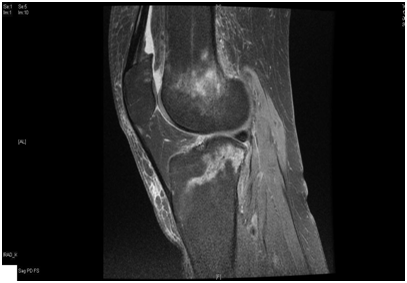

We present a 77 years old Caucasian female with spontaneous onset of pain in both knees for several weeks before presenting to the casualty then to our fracture clinic. There was no history of trauma. The patient is known to have Rheumatoid arthritis (RA) for over 30 years and has been on Bisphosphonate treatment (Alendronate) for over 24 months following the diagnosis of osteoporosis by DEXA scan. Plain radiographs showed subtle linear areas of sclerosis bilaterally in her proximal tibiae (Figure 1 & 2). Magnetic resonance imaging confirmed the presence of extra-articular linear high signal intensity change on T1, T2 with surrounding marrow edema consistent with insufficiency fractures in these areas as well as her right distal femur (Figure 3). These fractures were treated successfully with activity modification and weight bearing in a hinge knee brace as symptoms allows for six weeks along with physiotherapy input. Alendronate was stopped and Teriparatide (Recombinant PTH) was started.

Figure 1 AP & lateral radiograph of the left tibia showing an insufficiency fracture with osteosclerotic changes at the medial proximal tibia.